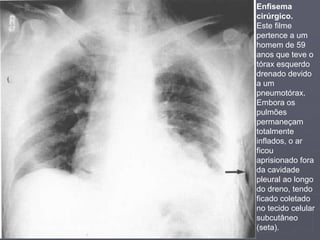

Enfisema

cirúrgico.

Este filme

pertence a um

homem de 59

anos que teve o

tórax esquerdo

drenado devido

a um

pneumotórax.

Embora os

pulmões

permaneçam

totalmente

inflados, o ar

ficou

aprisionado fora

da cavidade

pleural ao longo

do dreno, tendo

ficado coletado

no tecido celular

subcutâneo

(seta).